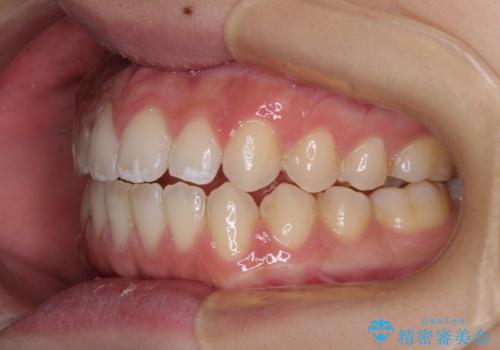

仕上がりとしては、もう少し上下前歯を接触させたかったのですが、ここまで改善されたことで患者様は大変満足され、治療を終えることとなりました。